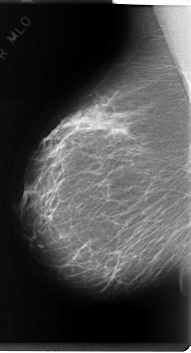

C_0220_1.LEFT_MLO

RIGHT_MLO LINES 6000 PIXELS_PER_LINE 3240 BITS_PER_PIXEL 12 RESOLUTION 50 NON_OVERLAY